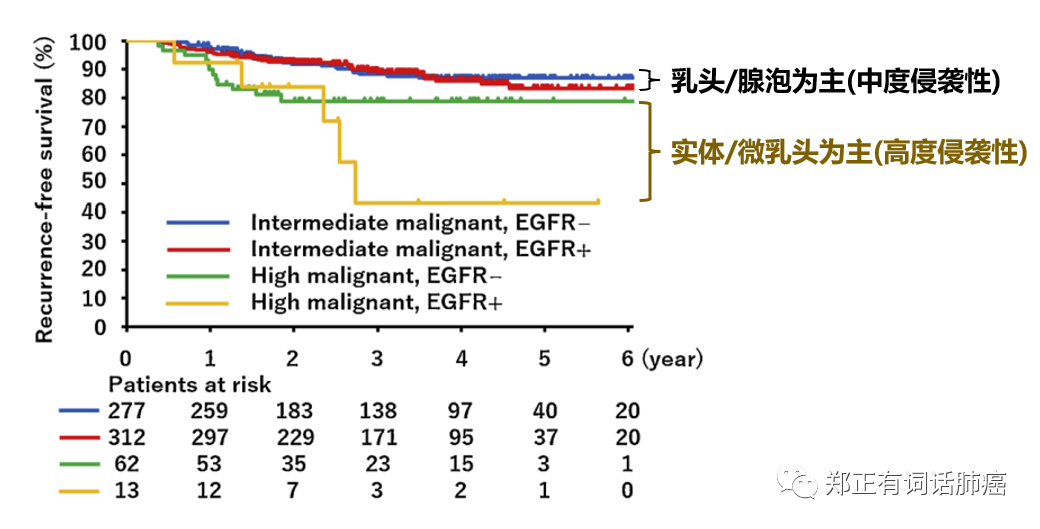

而在乳头/腺泡为主的中度侵袭和实体/微乳头为主的高度侵袭性群体,携带EGFR驱动患者均表现出更快的复发情况,其中,高度侵袭性者更甚。

而将突变状态/分期情况以及病理亚型杂糅一起进行分析后,我们可以得到以下表格: